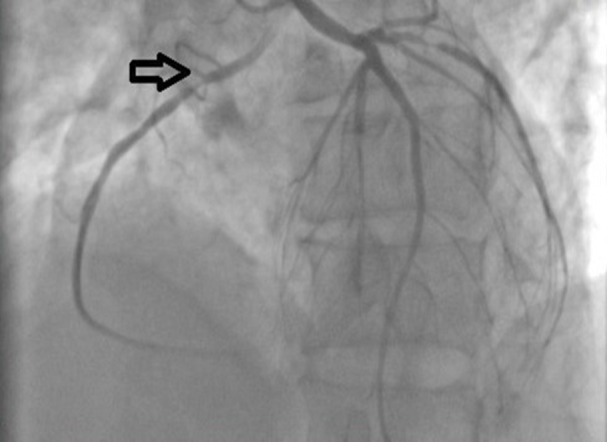

This case report examines a rare cardiovascular abnormality, the Aberrant Aortic Origin of the Right Coronary Artery (AAORCA), in a 75-year-old patient with a history of myocardial infarction, acute renal injury, and cardiogenic shock. Rapid medical intervention, including coronary angioplasty, demonstrated the significance of prompt care. Chronic issues, including tobacco use and left ventricular dysfunction, complicated matters, emphasizing the importance of comprehensive long- term therapy. This study underscores the critical clinical significance of AAORCA (Anomalous aortic origin of the right coronary artery) following the SCARE 2023 reporting criteria. This abstract emphasizes the delicate relationship between congenital defects, chronic hazards, and proactive healthcare in complex cardiovascular situations.